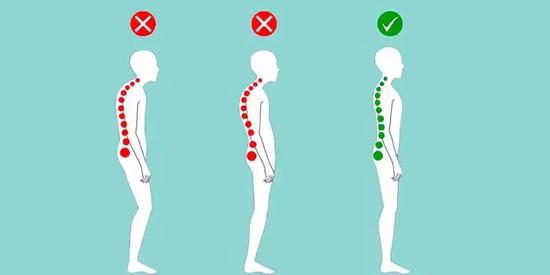

在站姿下,不管从正面或背面看,正常的脊椎排列应该是身体左右两边对称,并且正常的脊椎排列从上到下是呈一直线的。

如果在站姿下看到脊椎向身体的任何一边弯曲歪斜,就是有可能是脊椎侧弯,左右手臂与躯干之间的空隙不对称,右侧肩膀较高。

然而大部分的脊椎侧弯并不只有单一平面的左右倾斜,通常会伴随着脊椎旋转,往往也会影响到肩胛骨的动作,导致肩关节的活动度受限。

改善不良姿势

姿势不良与脊柱侧弯可互为因果,并恶性循环。因此控制脊柱侧弯的发展需重视不良姿势的纠正。抬头挺胸,勿弯腰驼背,尽量避免长时间翘二郎腿的姿势。